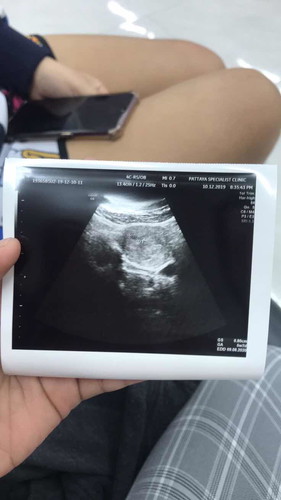

วันที่ 10.12.2019 อันนี้ที่เราซาวด์ครั้งแรกแล้วเกิดท้อง 5W2D แล้ว เราเลยอยากทราบว่าตอนนี้เราท้องได้กี่สัปดาห์แล้วค่ะ นับยังไงเราก็นับไม่ถูก?

4w คือ 1 เดือนค่ะแม่ ถ้าของคุณแม่ 5w 2d คือ1 เดือน 1 อาทิตย์และอีก 2 วันค่ะ

5 สัปดาห์ 1 เดือนกว่าๆคะ